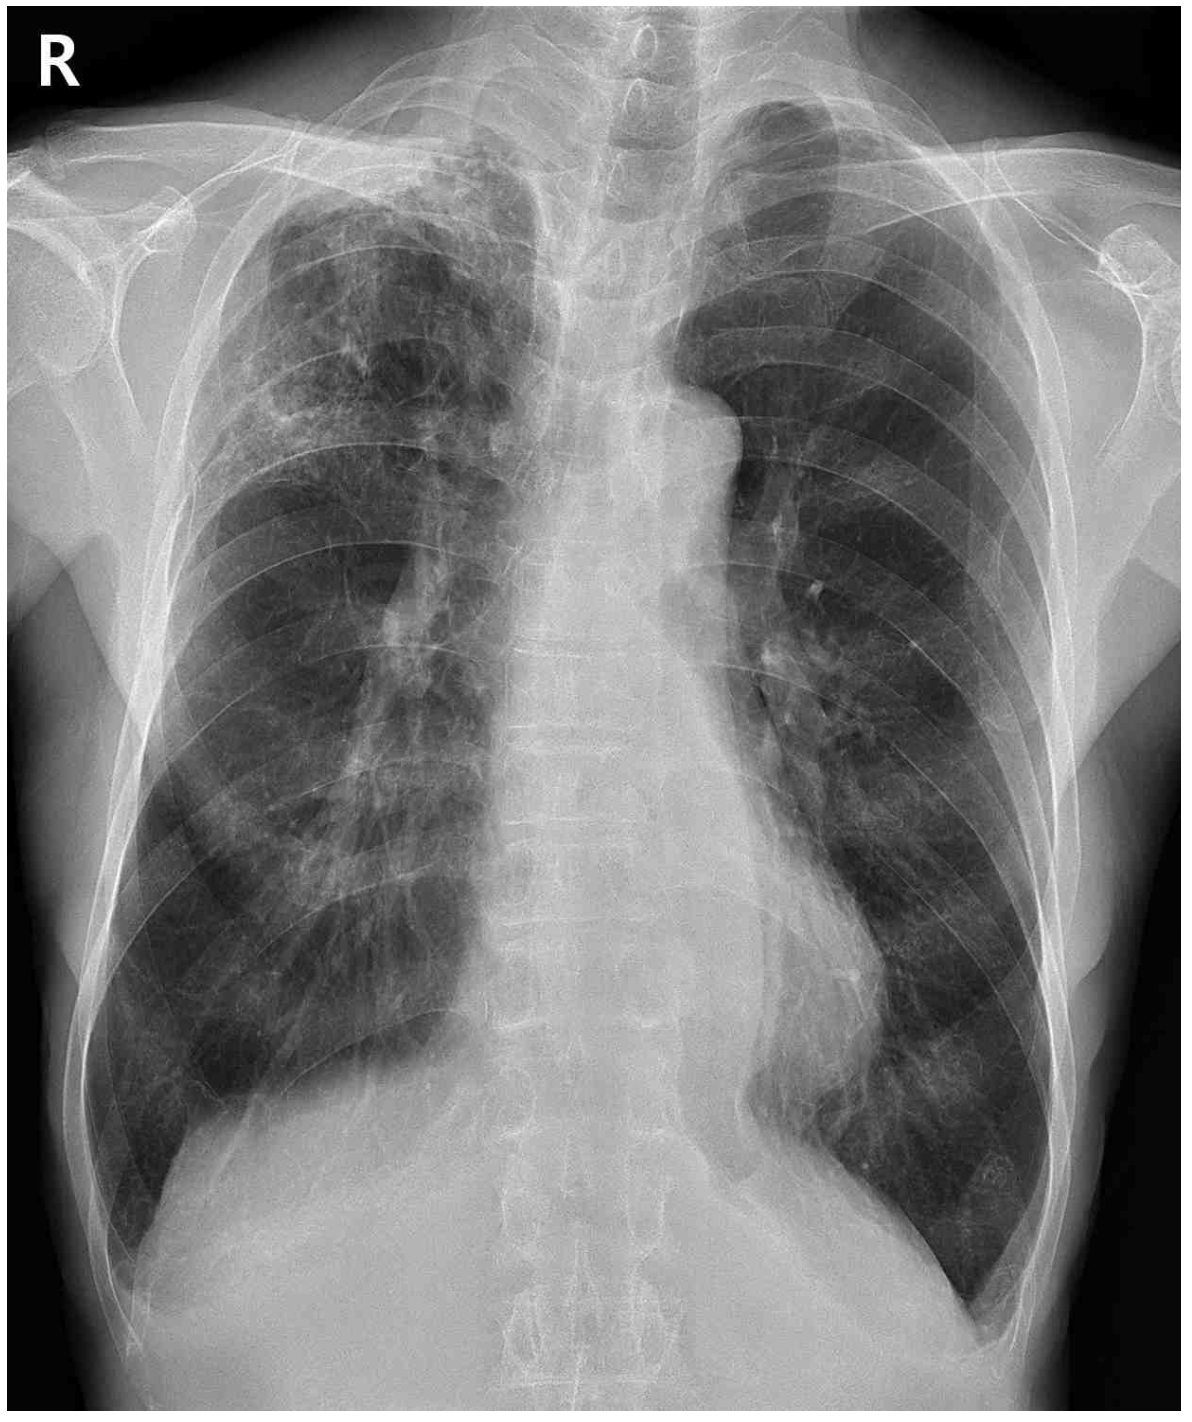

74세 남자가 6개월 전부터 기침을 한다며 병원에 왔다. 기침을 하면 가래가 조금 나오기도 하였다. 40갑•년의 흡연자 이다. 혈압 134/86 mmHg, 맥박 78회/분, 호흡 20회/분, 체온 37.1°C이다. 오른쪽 가슴에서 쌕쌕거림이 들린다. 가슴 X선사진과 가슴 컴퓨터단층촬영 사진이다. 가래검사 결과는 다음과 같다. 조치는?

CXR: RULF haziness

• CXR상 RULF hazziness가 발견되며 chest CT에서도 RULF에 centrilobular nodule 및 tree-in-bud pattern이 관찰된다. 만성 기침, 가래, 미열 등의 임상 양상과 영상 소견을 종합하여 판단할 때 폐결핵을 반드시 의심해보아야 한다.